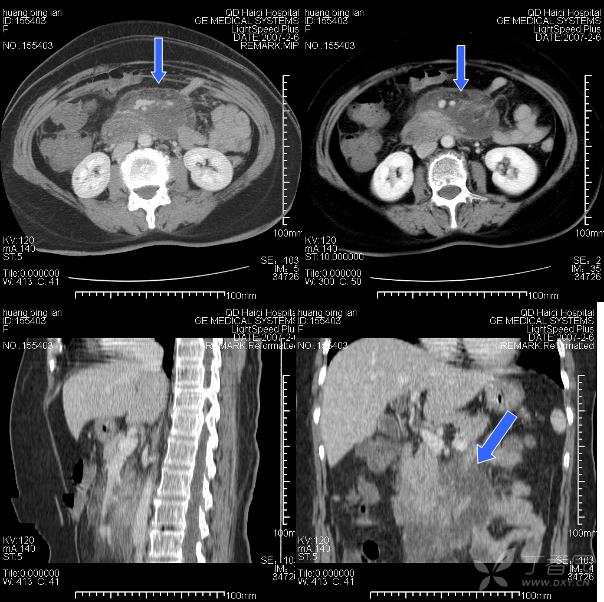

3 經腸系膜裂孔疝:transmesenteric hernia (TMH)

腸系膜是起自Treitz韌帶處,而止于回盲區的扇形腹膜折迭組織,腸系膜裂孔絕大多數為先天發育缺陷。裂孔的缺損大部在2~5 cm之間,疝入腸管多發生在回盲瓣以上50 cm處,故疝入腸管以回腸為主,占87%,易發生腸扭轉。結腸疝入者也見諸于文獻,約占9%。疝入的腸管60%發生絞窄。

臨床上TMH和經大網膜裂孔疝表現近似,發病率約占8%,TMH可分先天發育缺陷和獲得性兩種,70%發病在15歲以內,但平均年齡在50歲以上,說明老年人也是高發病人群,后者可因創傷、手術和炎癥所致。男女之比約為1∶2,視裂孔大小,臨床可出現疝入腸管退出情況,表現為反復發作的慢性過程,但大部份仍為急性腸梗阻甚至發生腸絞窄。

由于從裂孔疝出后并無一限制的疝囊,表現同于一般閉襻型腸梗阻,視裂孔大小,疝入腸管絞窄的嚴重性可能較之一般疝入陷窩者更甚。由于發生裂孔位置不定,又多在其游離緣,故無恒定的腹部CT定位,所以判斷進入疝囊內擁擠、擴張的閉攀腸管及受絞窄增粗、聚集的腸系膜血管非常重要。

急性腹痛,有腹部手術史。 手術診斷: 經腸系膜裂孔疝。